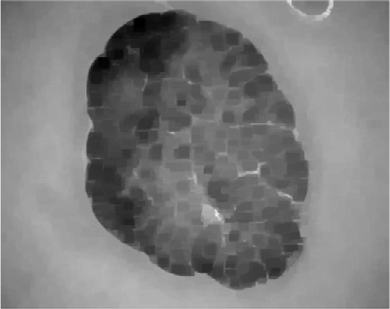

本研究中基于K均值的无监督分割用于检测和聚类所选皮肤镜图像,如图2 所示,使用了不同尺寸的边缘检测滤波器。图中图像具有不同的病灶大小、形状和皮肤表面粗糙度。图2C–E分别展示了使用索贝尔滤波器、普鲁伊特滤波器和非锐化掩模滤波器得到的聚类图像。红色轮廓表示ISIC 2016数据集中提供的相应皮肤病变的真实标签,而蓝色轮廓表示使用基于NS的K均值聚类结合不同结构的边缘检测滤波器检测到的皮肤病变区域。

图2

表明,使用窗口大小为 7×7的非锐化滤波器相较于同一滤波器的其他窗口大小以及其他滤波器类型(即Sobel和Prewitt算子)均取得了更优的结果。这些结果归因于非锐化滤波器能够锐化并增强高频分量,而高频分量代表了皮肤镜图像中的边缘。然而,所有滤波器在不同窗口大小下均未能识别ISIC_0010447皮肤镜图像中由同一病灶部分存在不同颜色区域和/或暗色区域引起的皮肤病变轮廓。